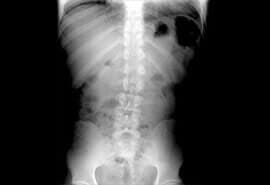

En el consultorio del Dr. Juan Fco. López Garza usted cuenta con la asistencia de un médico reumatólogo en Tampico, Tamaulipas especialista en el tratamiento de artritis reumatoide, tratamiento de osteoporosis y tratamiento de dolor de lumbalgia, así como para otros múltiples padecimientos.

está capacitado para diagnosticar a sus pacientes, dar seguimiento y control adecuado al problema que le causa una deficiencia en su sistema óseo en busca de eliminar el dolor de huesos y malestares que estos conllevan.

Espondilitis anquilosante

Osteoporosis